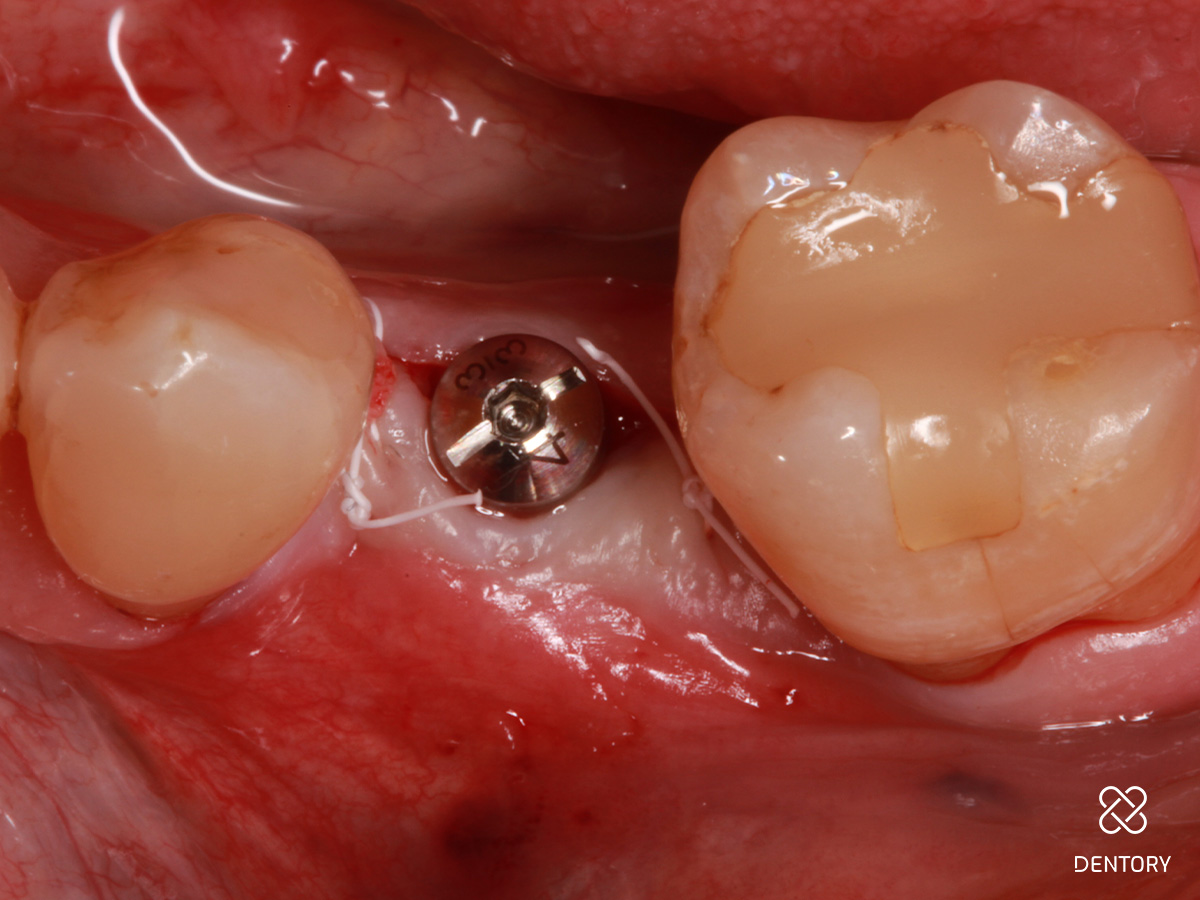

Abbildung 1

Ausgangssituation: Einzelzahnlücke regio 35.